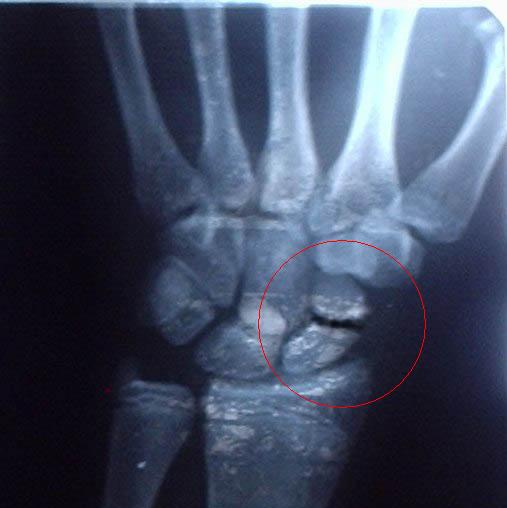

а ВОТ И МОЯ РУКА . СЛОМАЛ В АВГУСТЕ НЕ СРОСТАЕТСЯ ТАК ДО СИХ ПОР И КАТАЮСЬ.

Нажмите на изображение для увеличения

Название: gudron_911.jpg

Просмотров: 2613

Размер:	36.8 Кб

ID:	6041